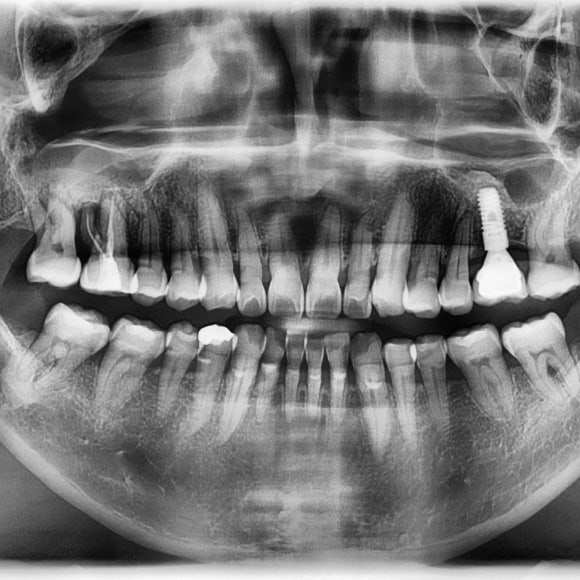

오른쪽 위 어금니,

뿌리주변 만성 염증으로 치아가 흔들리게 되면

녹아내린 뼈 자리에 염증 조직이 대체하게되면

씹을때 아프게되고

뼈가 없어진 만큼 뼈를 만들어야 하기 때문에

임플란트 준비기간만 10개월이 걸릴 수 있다.

해당 환자는

발치를 하고, 상악동 거상술과 뼈이식을 진행 하였음.

뼈가 단단해 질 때 까지 6개월 이상 충분한 치유기간을 준 후

보철물 머리를 올리게 될것.